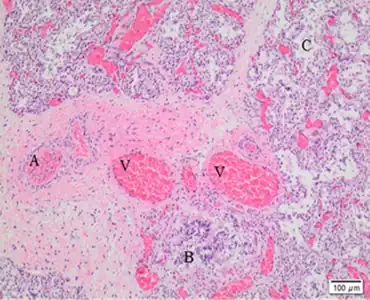

Dilated capillaries are not in contact with alveolar epithelium

How mutations affecting FOXF1 or its regulatory region cause ACD is unknown. ACD-causing mutations result in abnormal development of lung vasculature and alveoli. In ACD, the interstitium of alveoli is thickened, with few to no capillaries located at the alveolar surface to perform gas exchange, and with lower capillary density overall. This reduction in capillaries and their misplacement away from the alveolar surface result in poor oxygenation and retention of carbon dioxide in the blood and high pulmonary blood pressure.[1] There is also evidence of direct connections between pulmonary arteries and systemic vessels, which would deliver deoxygenated blood to the body, also contributing to low blood oxygenation.[4]

Another characteristic histologic finding is the presence of a pulmonary vein located next to a pulmonary artery and bronchus in the same bronchovascular bundle. In a normal lung, the pulmonary vein courses with lymphatic vessels in the lung septa.

The gold standard for ACD diagnosis is by examination of lung tissue under a microscope. The diagnosis is made if the pathologist sees the characteristic findings of ACD: misplaced pulmonary veins adjacent to pulmonary arteries, abnormal alveoli with thickened interstitia and abnormal capillary development. Due to the rapidly progressive course of ACD, this diagnosis is frequently made during autopsy. If ACD is suspected early, examination of tissue from lung biopsy results in the quickest diagnosis.[1] Genetic testing for FOXF1 is now available and can allow for slower but non-invasive diagnosis. As not all disease-causing mutations are known, false negatives or results of uncertain significance are possible with genetic testing.[2]